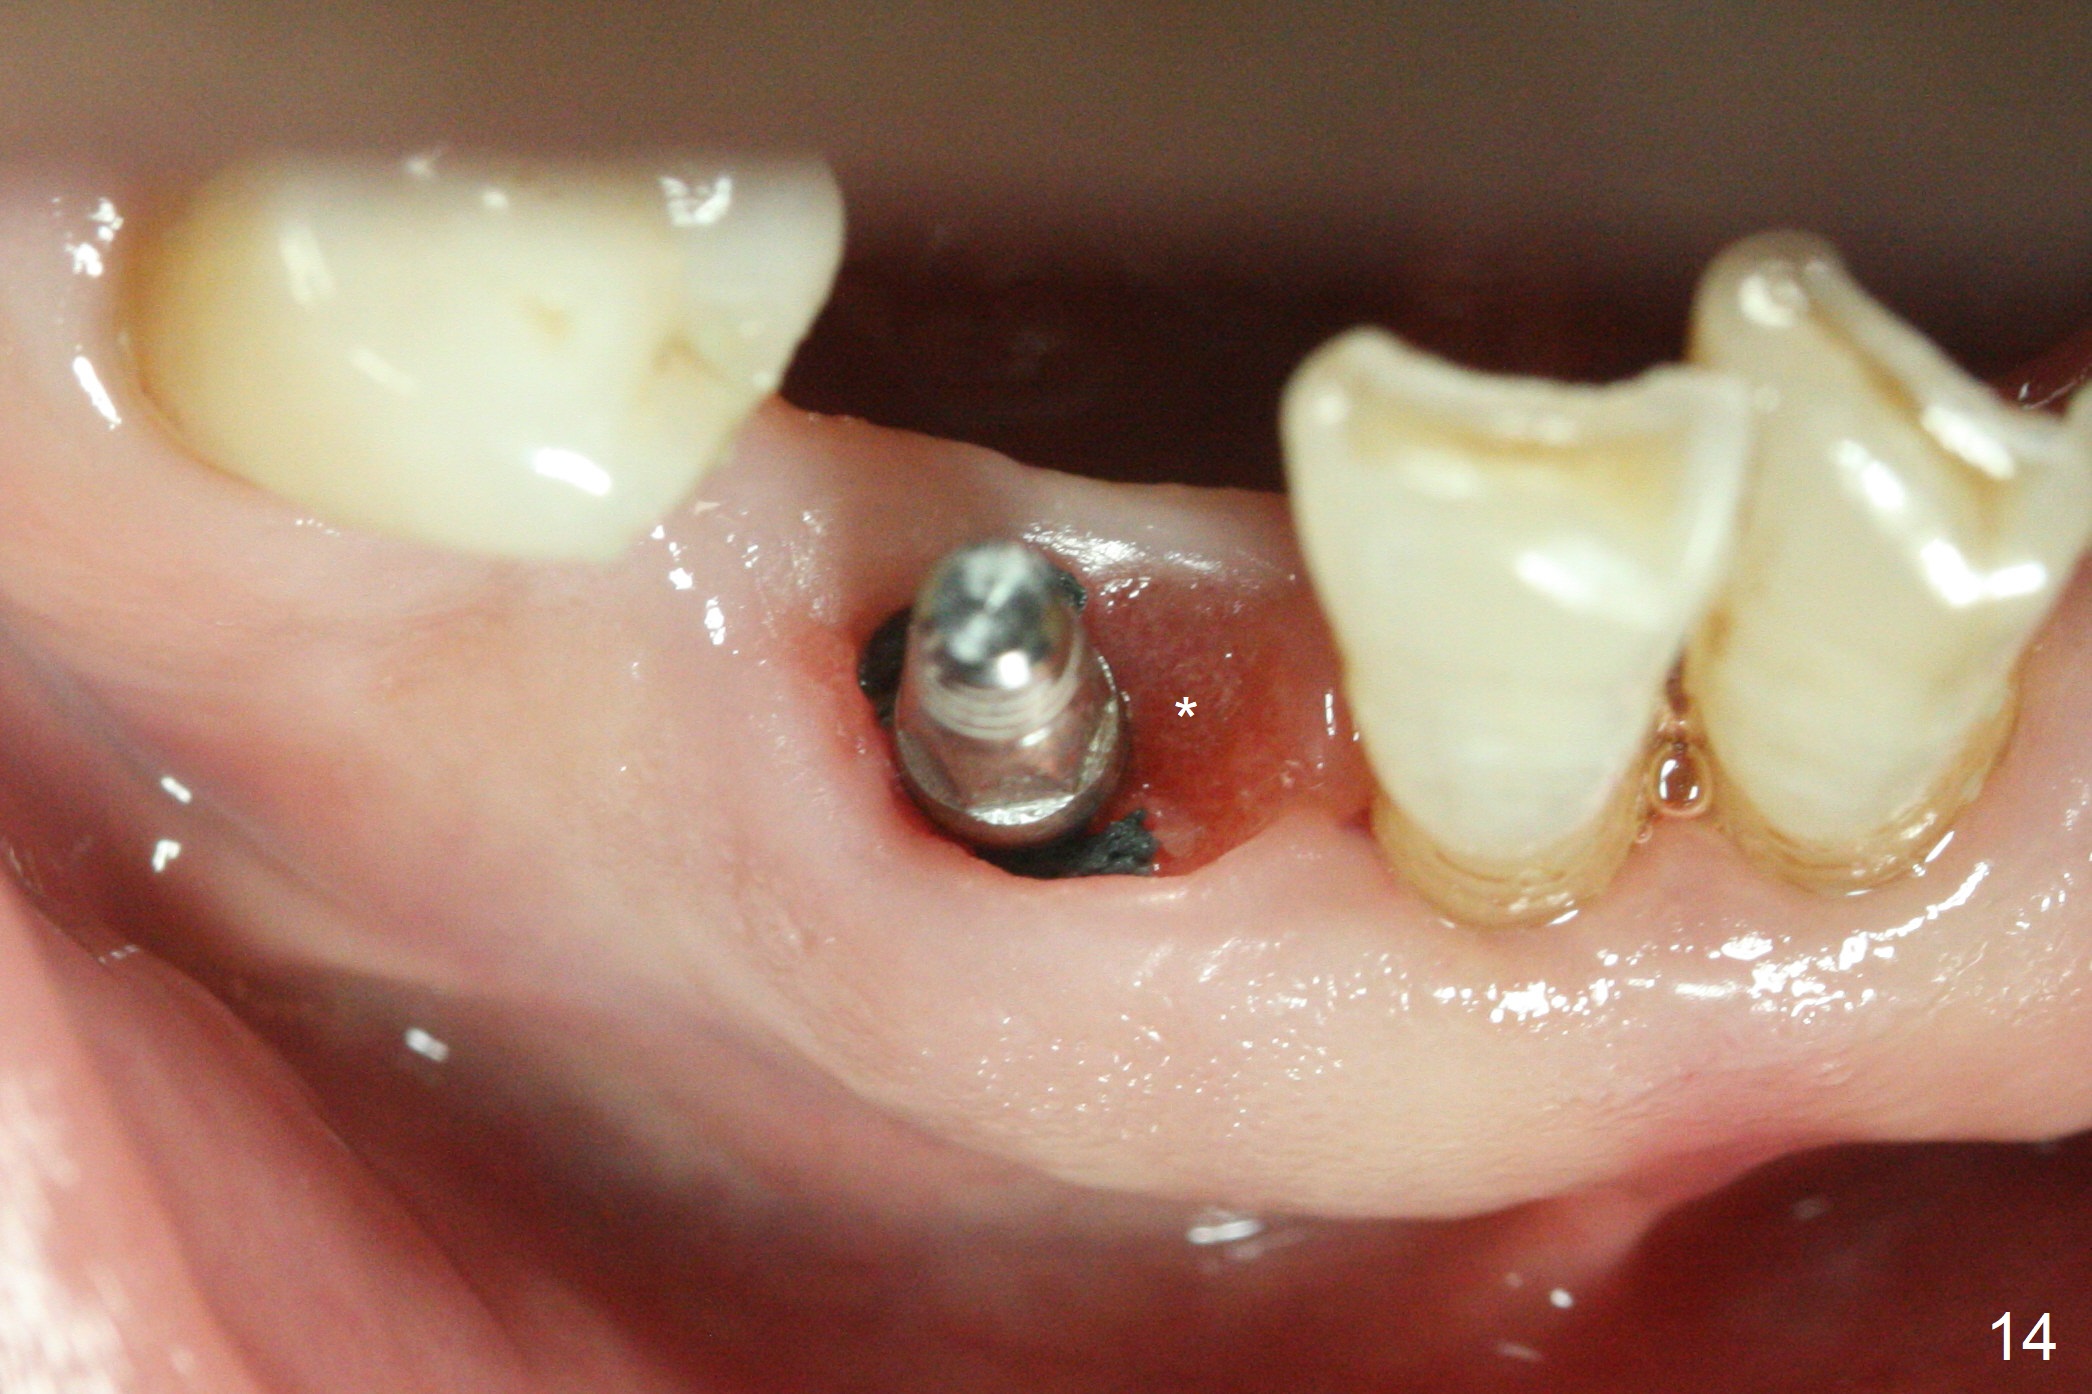

The lower dentition is special, consisting of a residual root (Fig.1 ^), 2 incisor (I), 1 canine (C), 1 premolar (P) and 1 molar (M). The residual root looks like an incisor with rotation of 90º (Fig.2,3). Osteotomy is initiated (Fig.4) for a 3x16(2) mm 1-piece implant (Fig.5 with 45 Ncm). The implant is being placed as distal as possible (Fig.4 arrow) so that a large canine-like provisional is to be fabricated in the large edentulous space (Fig.8,9) after bone graft (Fig.6,7 *). The gingiva around the provisional (Fig.10 P) remains healthy 11 days postop with occlusal clearance against the opposing dentition (Fig.11). The implant threads are not exposed with the help of bone graft 3 months 1 week postop (Fig.12). The gingiva around the implant is healthy (Fig.13). Soft tissue socket is formed by the provisional (Fig.14 *).